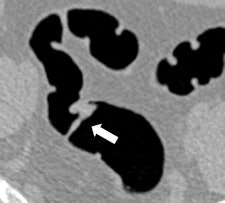

Along with his colleague Dr. Stefaan Gryspeerdt, Lefere has addressed CTC's potential pitfalls in a comprehensive paper published online January 4 in Insights into Imaging. Their top tips are to perform state-of-the-art CTC (preparation based on fecal tagging, along with colonic distension with CO2 plus injector, dual positioning, and smooth muscle relaxation), remember the general principles of interpretation, and take special care when examining the rectum and caecum.